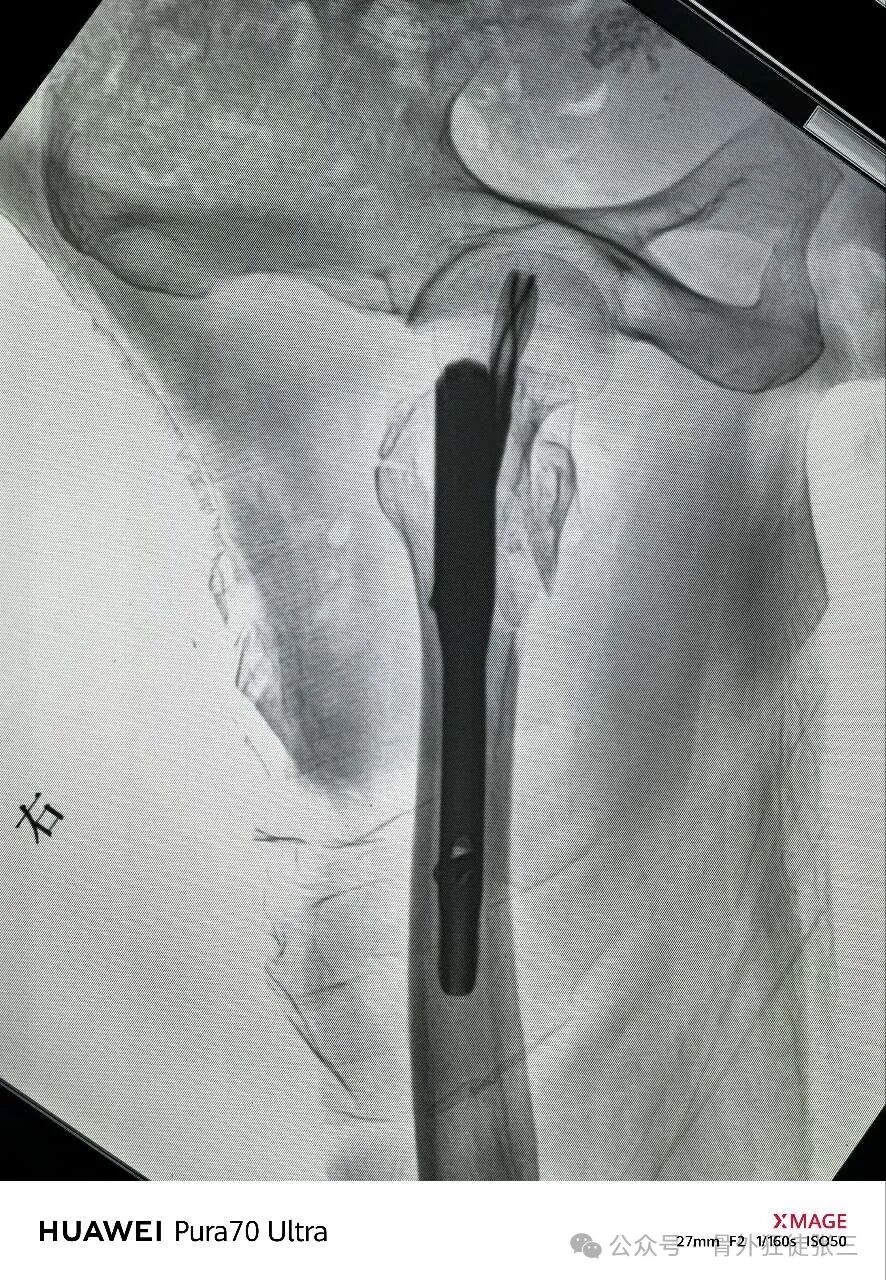

半截石位

手法复位后透视

正位复位不良

侧位复位欠佳